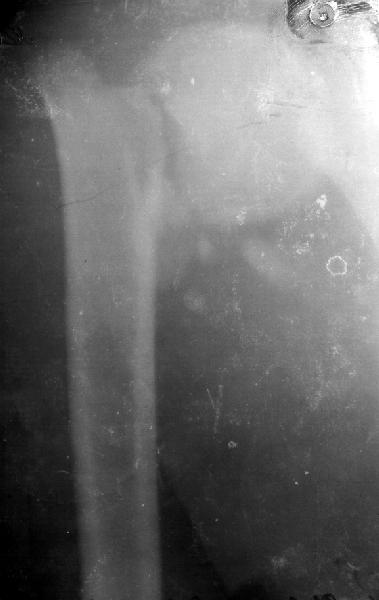

Мужчина 25 лет 16 августа 2002 г. в автоаварии получил перелом шейки плеча (снимок 1); 5 сентября в городской больнице выполнен остеосинтез пластинкой (снимок 2).К настоящему времени попал к нам на разработку ввиду выраженной контрактуры плечевого сустава. В течение последнего месяца беспокоят умеренные боли в области плечевого сустава, усиливающиеся при разработке, еще и торчит край пластинки. Нынешняя рентгенологическаякартина на снимках 3 и 4. Головка плеча уменьшается, сращение сомнительное.Кроме удаления пластинки, что еще на сегодня целесообразно сделать?Заранее спасибо.

Согласен с вашим мнением -асептический некроз головки плеча. Есть ли у вас надежды на реваскуляризацию головки ? Если надеетесь, то имеет смысл продолжать физио, если нет, то следует думать опротезировании.

I think the AVN is at least stage 3 with deformity of the head. I would advise a removal of implant and a cementless humeral head replacement. Or if you have the experience and the implant, as well as adequate bone stock, maybe a resurfacing prosthesis like the Copeland shoulder. I am not sure if you can do it one or two stages. You can perhaps do it in one stage if there is no sign of infection and if the patient condition allows it. You should not worry too much about age since this is a non